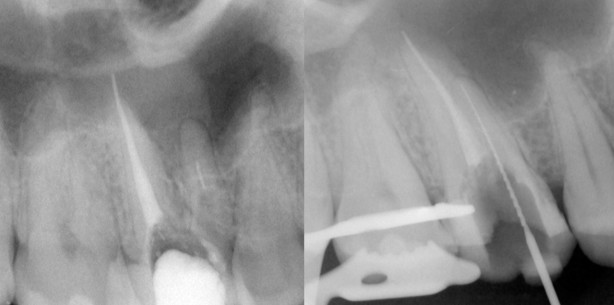

Patient N.M. wünscht eine Drittmeinung, zwischenzeitlich hatte er bereits einen zweiten Zahnarzt konsultiert. Dieser bestätigte eine insuffiziente Wurzelfüllung und vermutete eine Instrumentenfraktur im mb1 (Abb. 1).

Mittels Röntgenaufnahme lässt sich ein frakturiertes Instrument in mb1 vermuten. Des Weiteren scheint es, als sei der distale Wurzelkanal sowie der mb2 nicht abgefüllt worden, was sich zu einem späteren Zeitpunkt der Behandlung bestätigen soll te. Der Patient wurde vom vorbehandelnden Zahnarzt über die Fraktur nicht aufgeklärt.